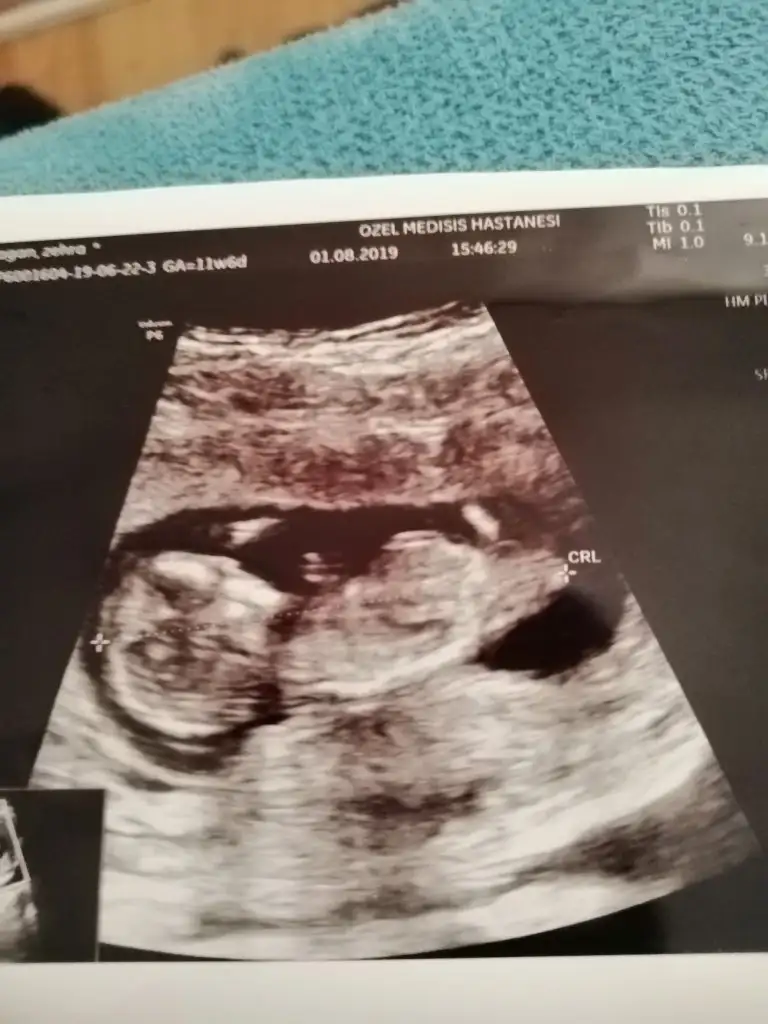

Erkek gibi11 haftalıktahmin alabilirmiyim

Erkek gibi kafa sekline yorumluyorum nub artık olmaz 13 hafta sanırımArkadaşlar daha önce yorum yapmıştınız ama doktor kesin bişey söylemiyor bunada bakabilir misiniz

Tam dik degil ama ben tahminimi Erkek gibi yorumluyorum